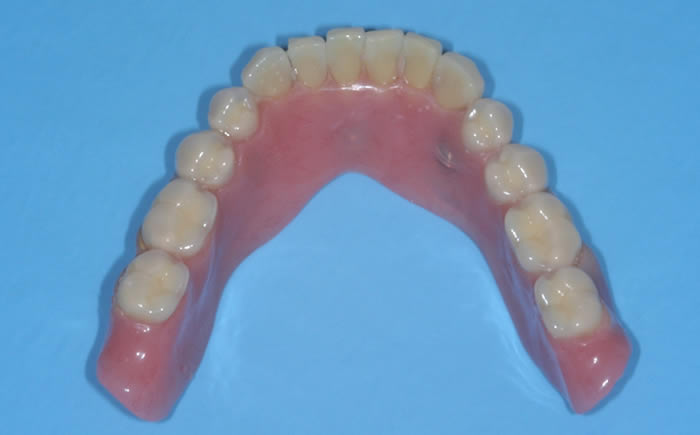

Loose dentures secured by dental implants

Case One (5 images)

Three dental implants used to secure a loose lower denture.